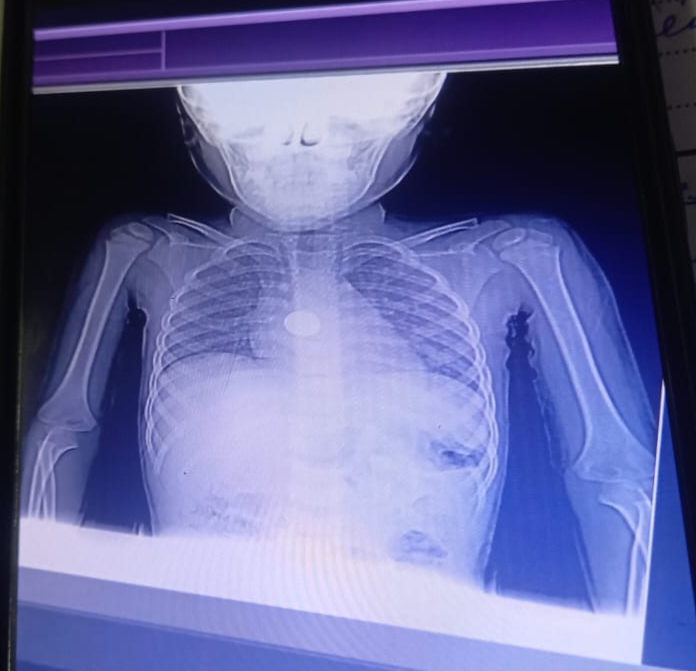

وأوضح الدكتور أحمد البيلي وكيل وزارة الصحة، أن فريق قسم المناظير بمستشفى أبو كبير المركزي قام بإجراء منظار عاجل وذات مهارة لإنقاذ الطفل صاحب الـ ٥ سنوات، حيث تم استقباله في ساعة مبكرة من فجر اليوم وهو يعاني من ابتلاع بطارية معدنية صغيرة، وهي من الحالات شديدة الخطورة نظرًا لقدرة البطاريات على تفريغ شحنتها داخل الجسم خلال دقائق قليلة، مما قد يسبب حروق عميقة بالمريء وقد يصل الأمر إلى حدوث ثقوب أو نزيف حاد يهدد حياة الطفل، مضيفاً أنه فور استقبال الحالة، تم التنسيق الفوري من خلال مركز الخدمات الطارئة بالمديرية، وتم إجراء الفحوصات الطبية اللازمة، ثم التدخل بالمنظار لاستخراج البطارية من المريء في الوقت المناسب دون حدوث أي مضاعفات، مع متابعة مباشرة وتدخل سريع من الفريق الطبي خلال الساعات الأولى من الصباح.